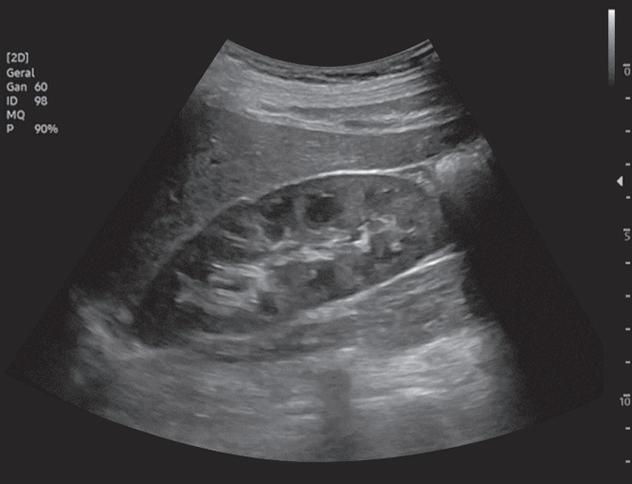

Fig. 2-18. Nódulo na bexiga com vascularização ao Doppler.